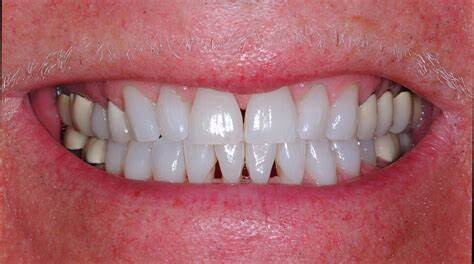

Have you lost gum from between your teeth? If you look at any magazine photo or advertisement you will see cosmetically beautiful smiles with uniform, straight teeth. The smiles you see in these magazines do not have gaps or spaces. If you have tiny triangles between two or more of your teeth, you may feel self conscious about their appearance.

Unfortunately, lost gum between teeth can indicate that the tissue is not as healthy and strong as it should be. Often, gum treatment is needed before cosmetic alterations can be made to fill these spaces. Good oral hygiene is important for your teeth and gums and patients are encouraged to improve how they brush and floss. Once your gums have been treated and are healthy, treatment for the dark spaces can be done. You can say goodbye to these black spaces in your smile through one of three treatment options.

Veneers:

Crafted from very thin pieces of ceramic, veneers act as a type of cover for your front teeth. They can camouflage a host of cosmetic issues in an otherwise healthy, functional dentition. Often old composite veneers are replaced with porcelain. Dental veneers are one of the best ways to improve the cosmetic appearance of teeth in a relatively short amount of time. It often takes just a couple of appointments to receive the veneers to camouflage the host of esthetic issues, including spaces between your teeth. However, due to their custom fabrication and design, ceramic veneers are pricier than other cosmetic treatments. Dental veneers last on average 15 to 20 years before needing replacement. Most clients who choose them feel that veneers are worth it.

Gum disease will often cause recession of tissue from around and between your teeth. The gum between your teeth is called the interdental papillae. Losing the papillae produces the dark space. The black spaces will be more pronounced when your teeth shapes are triangular/trapezoidal in shape. Simply sanding the contact points of crowns to a more square shape will broaden the contact point between the crowns. As the teeth move closer, these spaces close down by pinching the gum papillae.